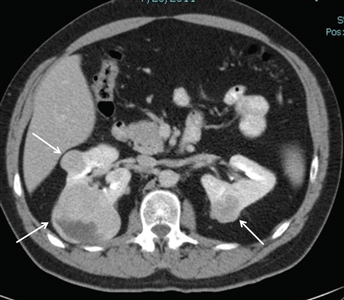

Del 25 % al 35 % de las personas afectadas por el síndrome de BHD presentarán tumores renales,[1,4,10,11] que son multifocales en el 65 % de los casos y, a menudo, bilaterales. La frecuencia de tumores renales en los pacientes con síndrome de BHD fue del 20 % según la revisión de historias clínicas y del 29 % según la evaluación mediante TC. La mayoría de los tumores renales relacionados con el síndrome de BHD son de crecimiento lento. La mediana de edad en el momento del diagnóstico oscila entre 48 y 50 años (intervalo, 31–71 años).[2,12,13,14] Los tumores renales fueron más frecuentes en los hombres que en las mujeres (27 hombres; 11 mujeres). Los tumores renales relacionados con el síndrome de BHD surgen a una edad más temprana que las formas esporádicas del cáncer de células renales (RCC), cuya mediana de edad es de 64 años en el momento del diagnóstico.[15] En la Figura 1 se observan tumores renales bilaterales en un paciente con síndrome de BHD.